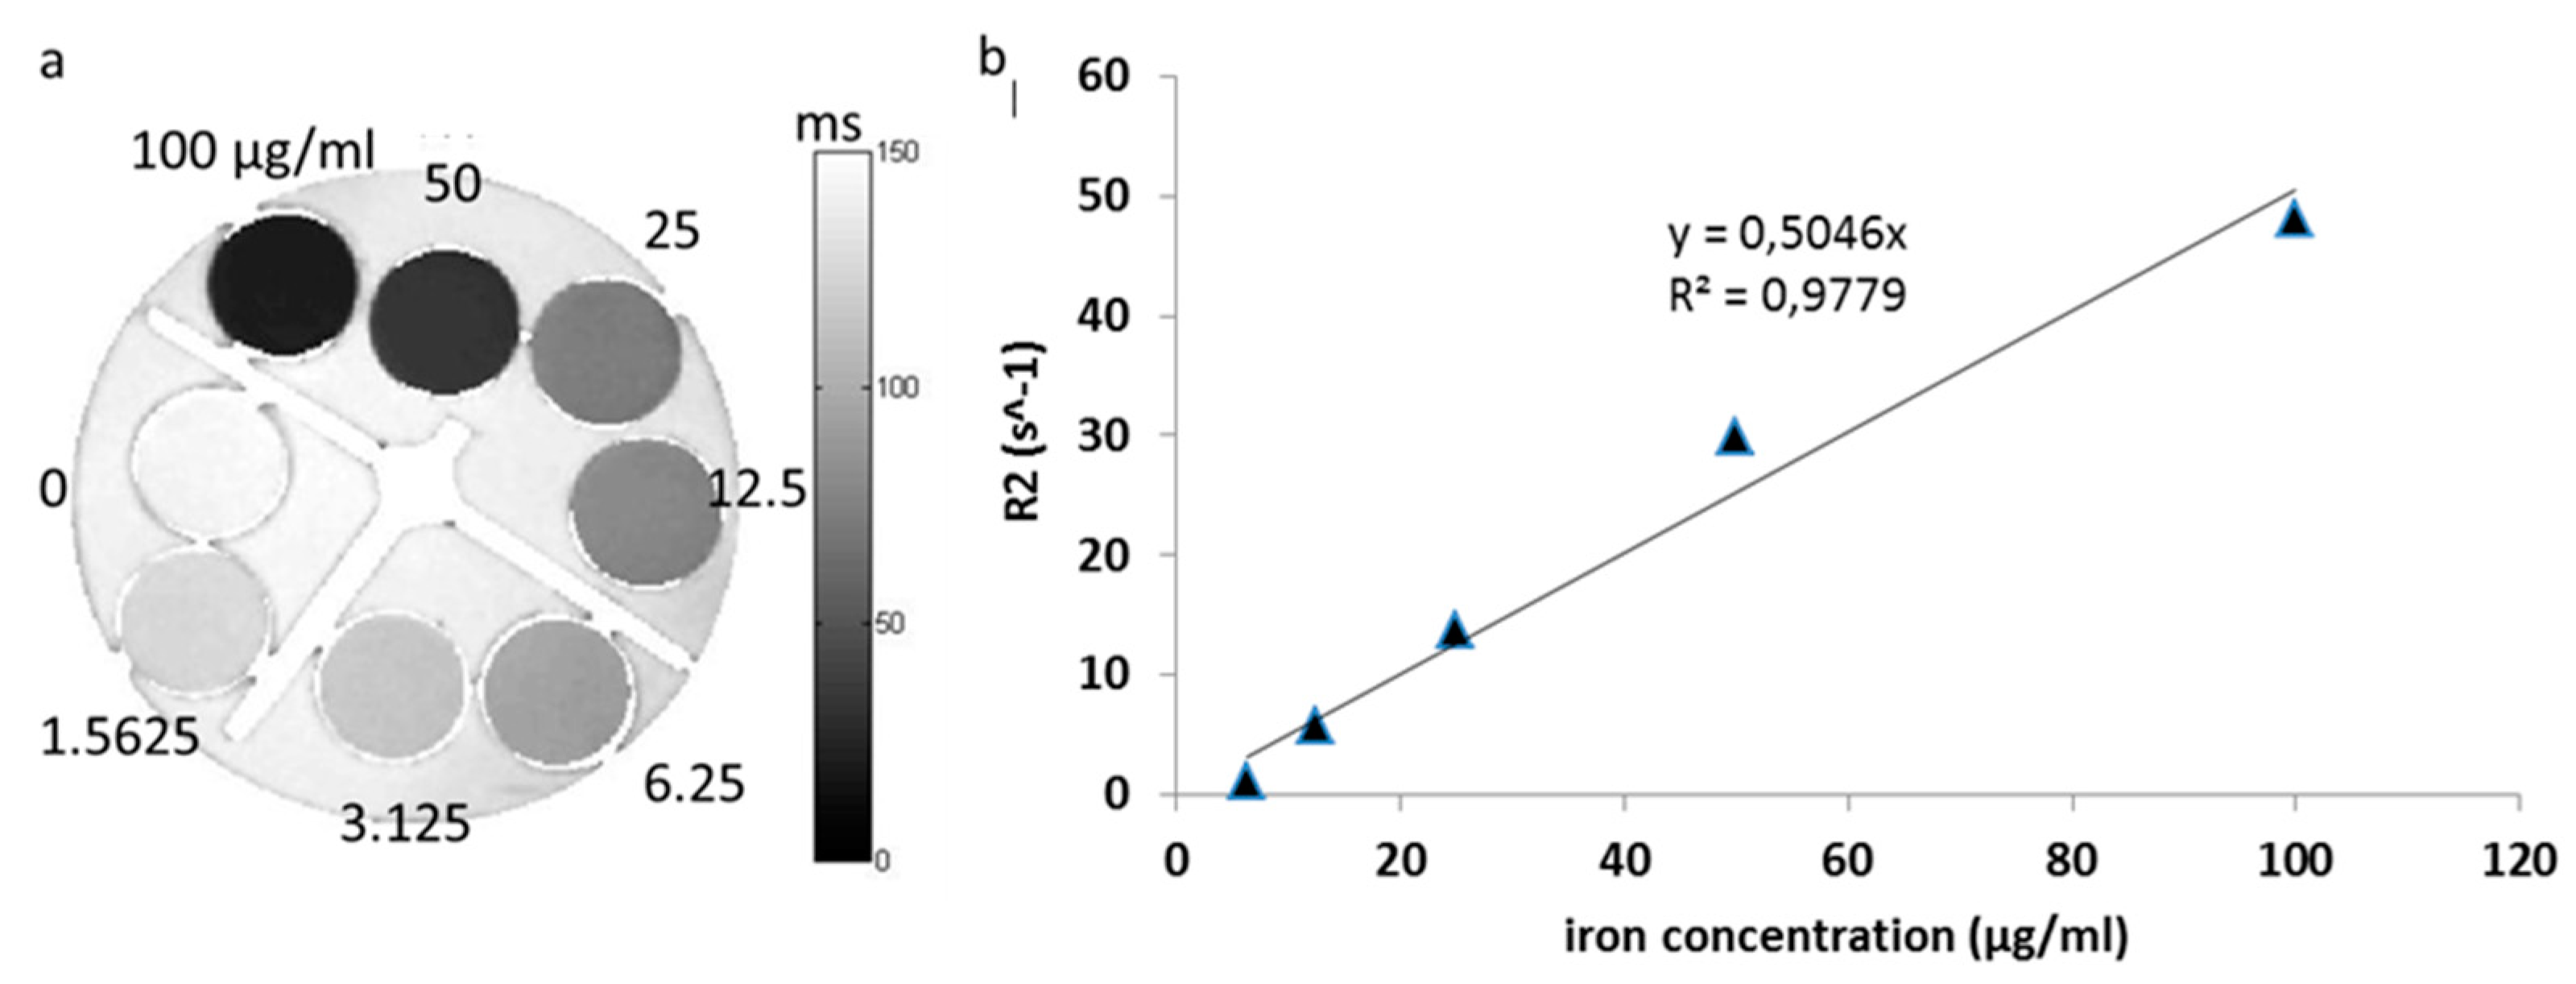

3.5. Magnetic Resonance Imaging

3.5.1. T2 Relaxation of Nanoparticles

3.5.2. In Vitro T2 Relaxation